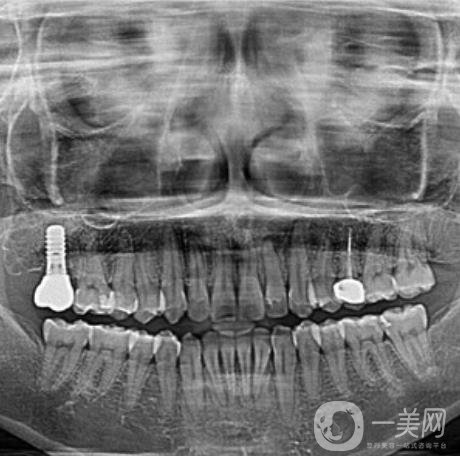

三、天津爱齿口腔种植牙案例

我掉的那颗牙齿是因为我咬东西的时候不小心要掉了一半,后来牙齿松动直接就掉了。估计大家可能还会嘲笑我怎么这么没出息,吃东西都可以把自己的牙齿给割掉,其实我想说的是实在是太寸了,真的没有想到我的牙齿会这么脆弱。有一个牙洞实在是太别扭了,到口腔医院让医生给我看了一下,说是可以做种植牙这个手术来补上之前那个牙洞。医生简单的和我说了一下,种植牙是一个怎么样的手术,以及手术的大概过程和术后修复。

做完种植牙已经四个半月的时间了。现在我的那颗牙齿早就已经种好了。在种好了之后我特别小心的使用着,可牙齿医生还告诉我这颗牙齿是特别坚固的,比我自己长的那些牙齿还要兼顾,让我放心好了,现在的我吃东西一切都恢复了正常。我感觉*近几天都让我长胖了,毕竟每天胡吃海塞的。